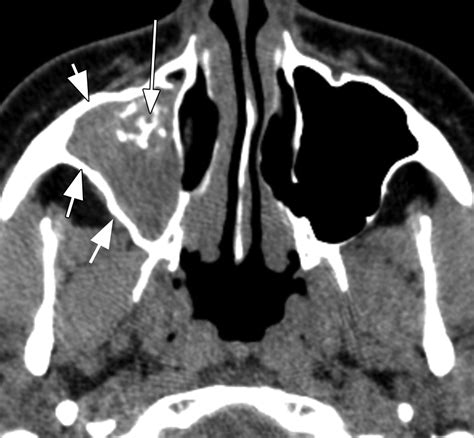

• Invasive Fungal Sinusitis: This is a serious medical emergency, typically seen in individuals with severely compromised immune systems (such as those with uncontrolled diabetes, transplant recipients, or cancer patients). It requires immediate and aggressive intervention.

Imaging (CT Scan) Mucosal thickening High-density spots or calcifications

• Computed Tomography (CT) Scan: This imaging provides a detailed view of the sinuses and can highlight calcifications or specific patterns characteristic of fungal growth.

Invasive cases require urgent surgical debridement (removal of infected tissue) alongside systemic (oral or intravenous) antifungal therapy. In all cases, treating any underlying issues, such as poor drainage or systemic immune compromise, is critical for long-term resolution.